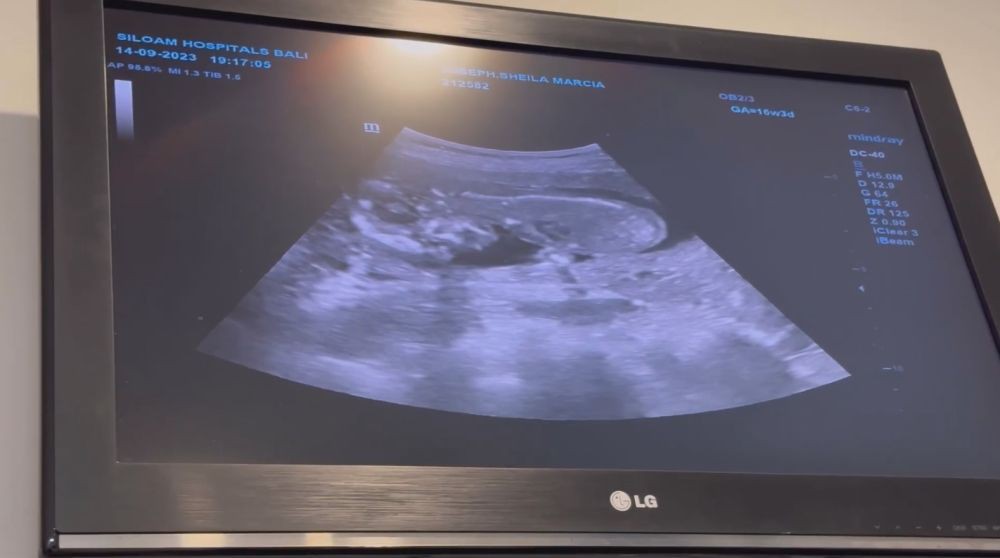

5. Tampak dari hasil USG di layar, kehamilan Sheila sudah memasuki usia 16 minggu lebih 3 hari pada 14 September.